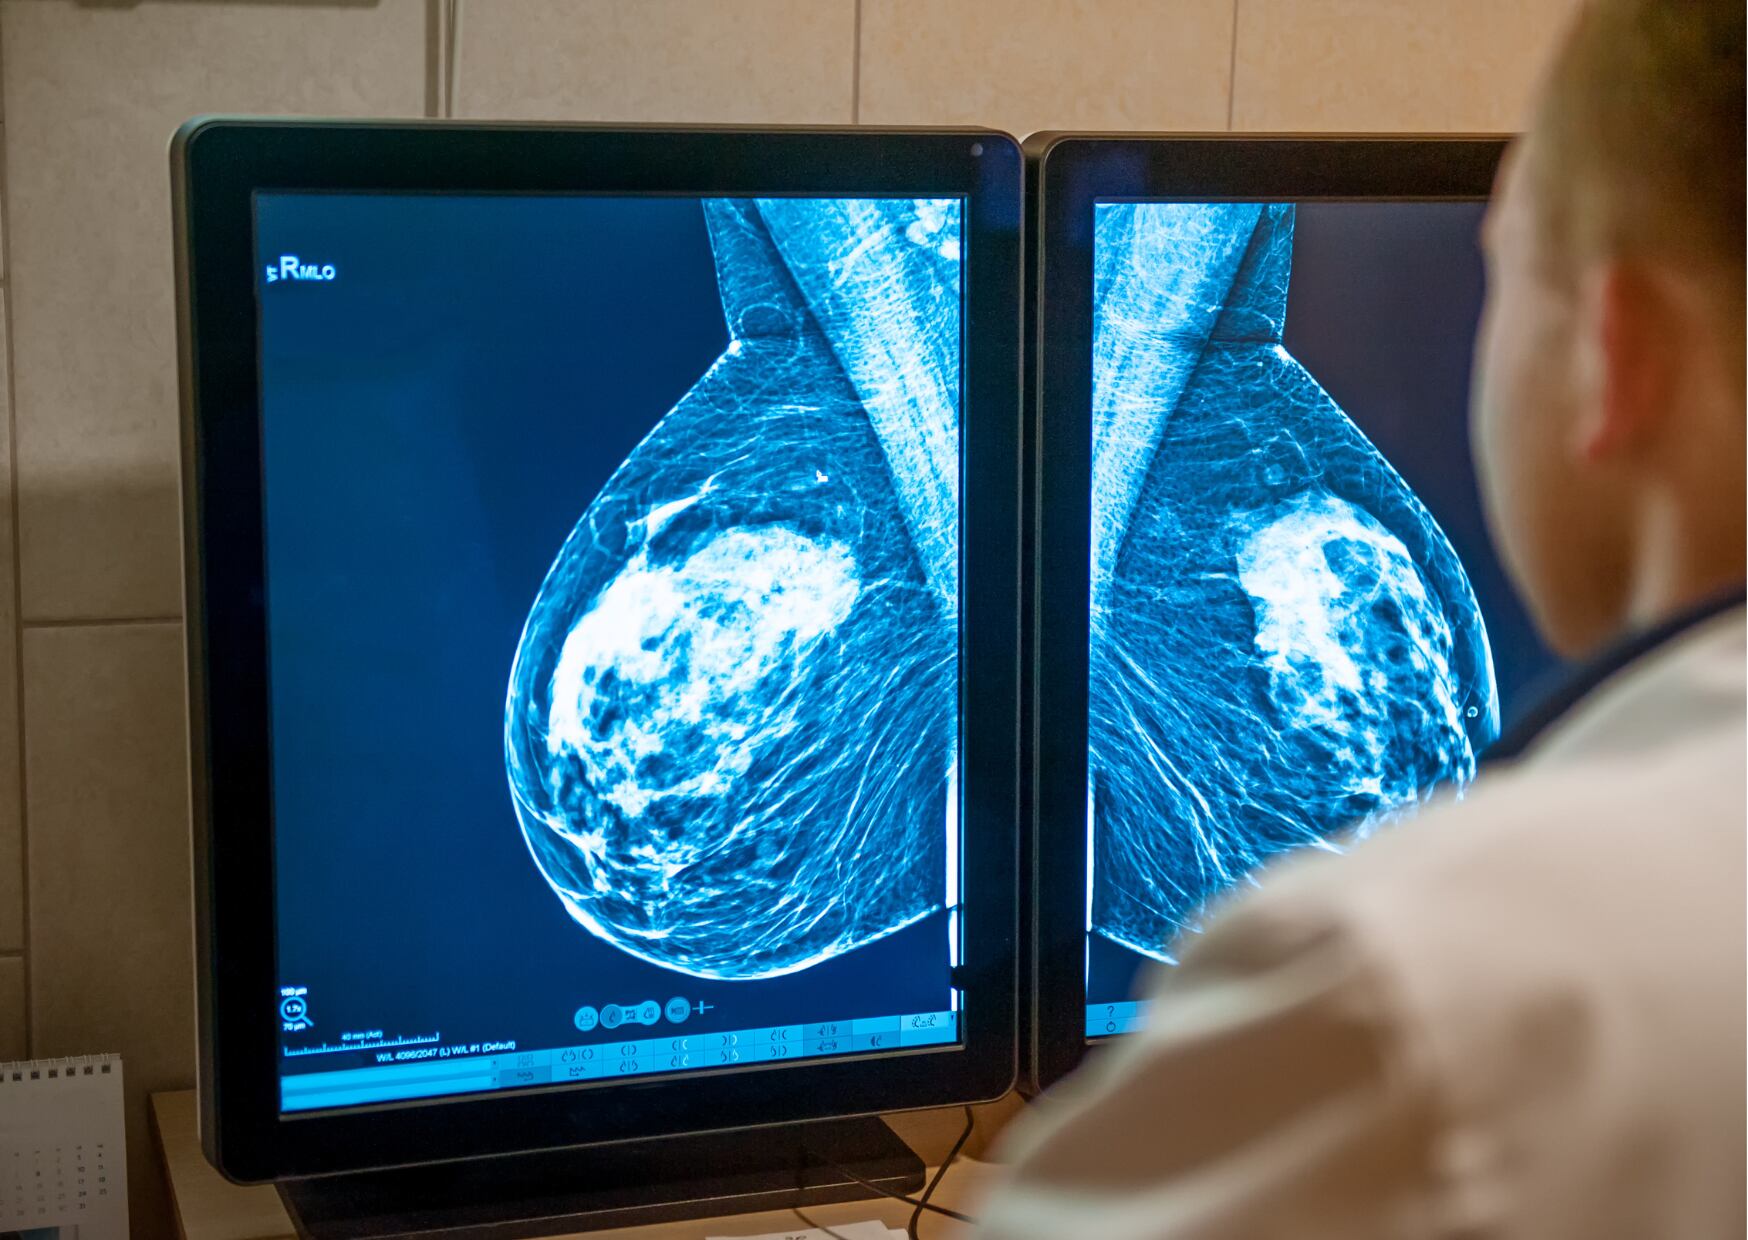

¿Por qué el autoexamen es insuficiente? Son varias las razones. Por un lado, porque, por más autoconocimiento que tengamos de esta parte del cuerpo, las mujeres no tienen la habilidad de palpar cosas que un profesional en salud sí puede sentir. Por otro lado, hay exámenes como ultrasonidos y mamografías con capacidad de detectar anomalías más pequeñas que las que pueden descubrir las manos.

- Asistir a consultas médicas con regularidad, que impliquen una mamografía cada dos años en mujeres mayores de 40 años.